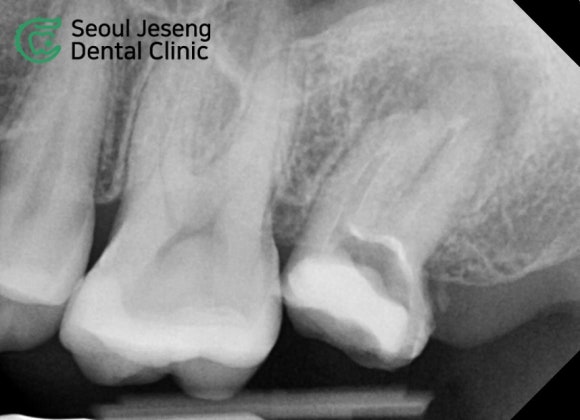

치료 전 후의 CT 사진입니다.

상악동으로 뚫고 나가려는 염증 자리에

다시 튼튼한 뼈가 재생되는 것을 보실 수 있습니다.

5개월이라는 긴 시간 동안 환자분께서는 꾸준히 내원하시며 적극적으로 치료에 임해주셨습니다.

그 결과, 상악동과 치아 사이에 뼈가 다시 재생되는 것을 볼 수 있었고, 저작 시 느껴지던 불편감도 모두 사라졌습니다.